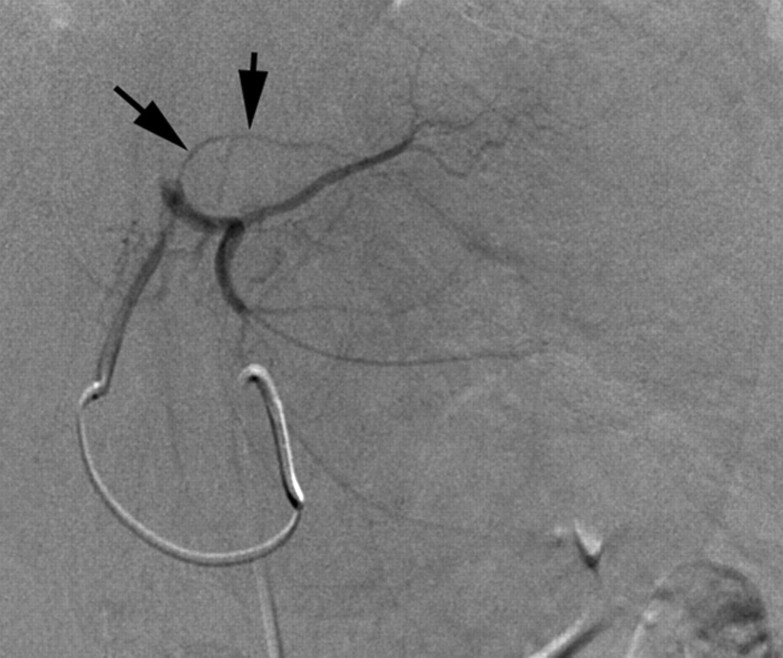

Optimal utilization of all transcatheter therapies requires knowledge of variant hepatic anatomy (27). This is critical for both appropriate targeted therapy delivery and the prevention of complications. Specifically, awareness of extrahepatic vessels arising from the hepatic arteries (28,29) is critical to prevent toxicities from nontarget embolization. Figure 1 delineates many of the extrahepatic arterial pathways that are of interest in these procedures. The prospective identification of these nontarget vessels can minimize the risk of adverse events related to the extrahepatic deposition of the therapeutic agent.

Figure 1a:

Common extrahepatic arteries that need to be recognized and potentially embolized prior to transcatheter intraarterial therapy. (a) Celiac angiogram reveals right gastric artery (arrows) originating from the proximal left hepatic artery. (b) Right hepatic angiogram reveals cystic artery (arrow) originating from the proximal right hepatic artery. (c) Celiac angiogram in a patient with a replaced right hepatic artery from the superior mesenteric artery. Arrows delineate a faint linear vessel coursing from the segment IV branch of the left hepatic artery. (d) Selective left hepatic angiogram better demonstrates the falciform artery (black arrows). The tumor blush is now visible (white arrows). (e) Left hepatic angiogram reveals an accessory left gastric artery (arrows). (f) Delayed phase selective angiogram of the accessory left gastric artery shows the draining coronary vein (arrow), confirming gastric perfusion. (g) Celiac angiogram reveals arterial-portal fistula in the right hepatic lobe. Off the left hepatic artery, there is a vessel coursing under the left hemidiaphragm (arrows). (h) Left hepatic angiogram better demonstrates this vessel (arrows) as the left inferior phrenic artery.